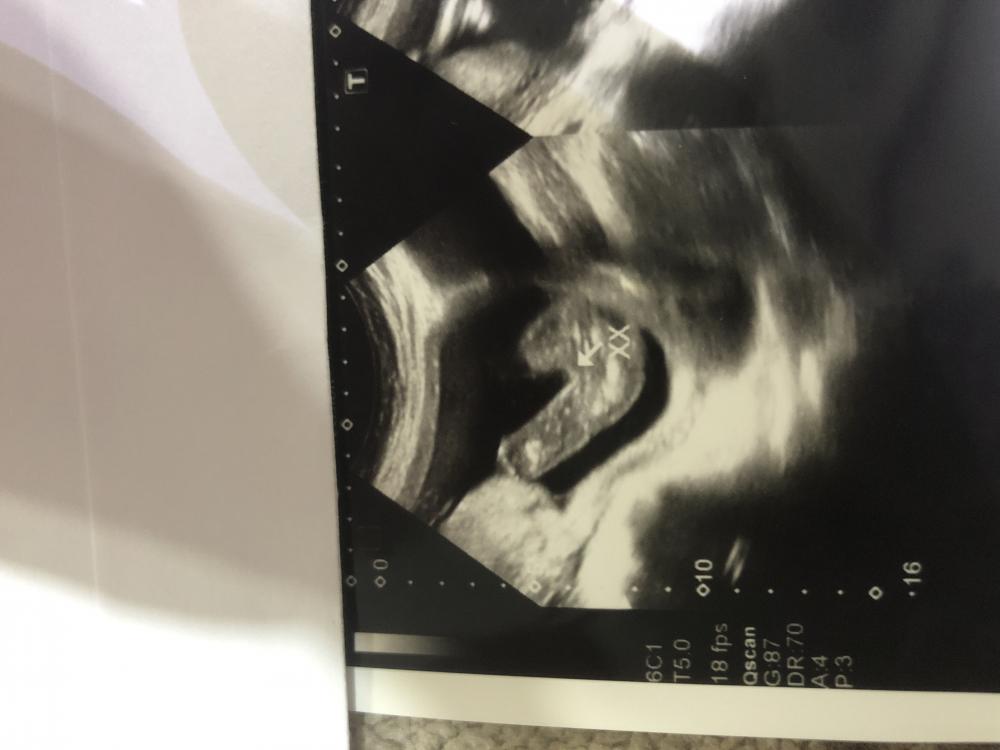

يابنات شوفو الصورة وقولو تعليقكم وش باين معاكم

ماعرف صراحه